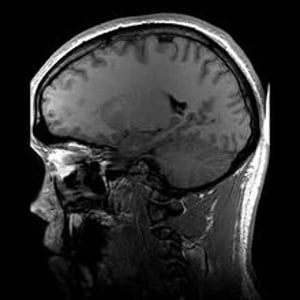

Magnetic resonance imaging (MRI) is a medical imaging technique used in radiology to form pictures of the anatomy and the physiological processes of the body in both health and disease. MRI scanners use strong magnetic fields, radio waves, and field gradients to generate images of the organs in the body.